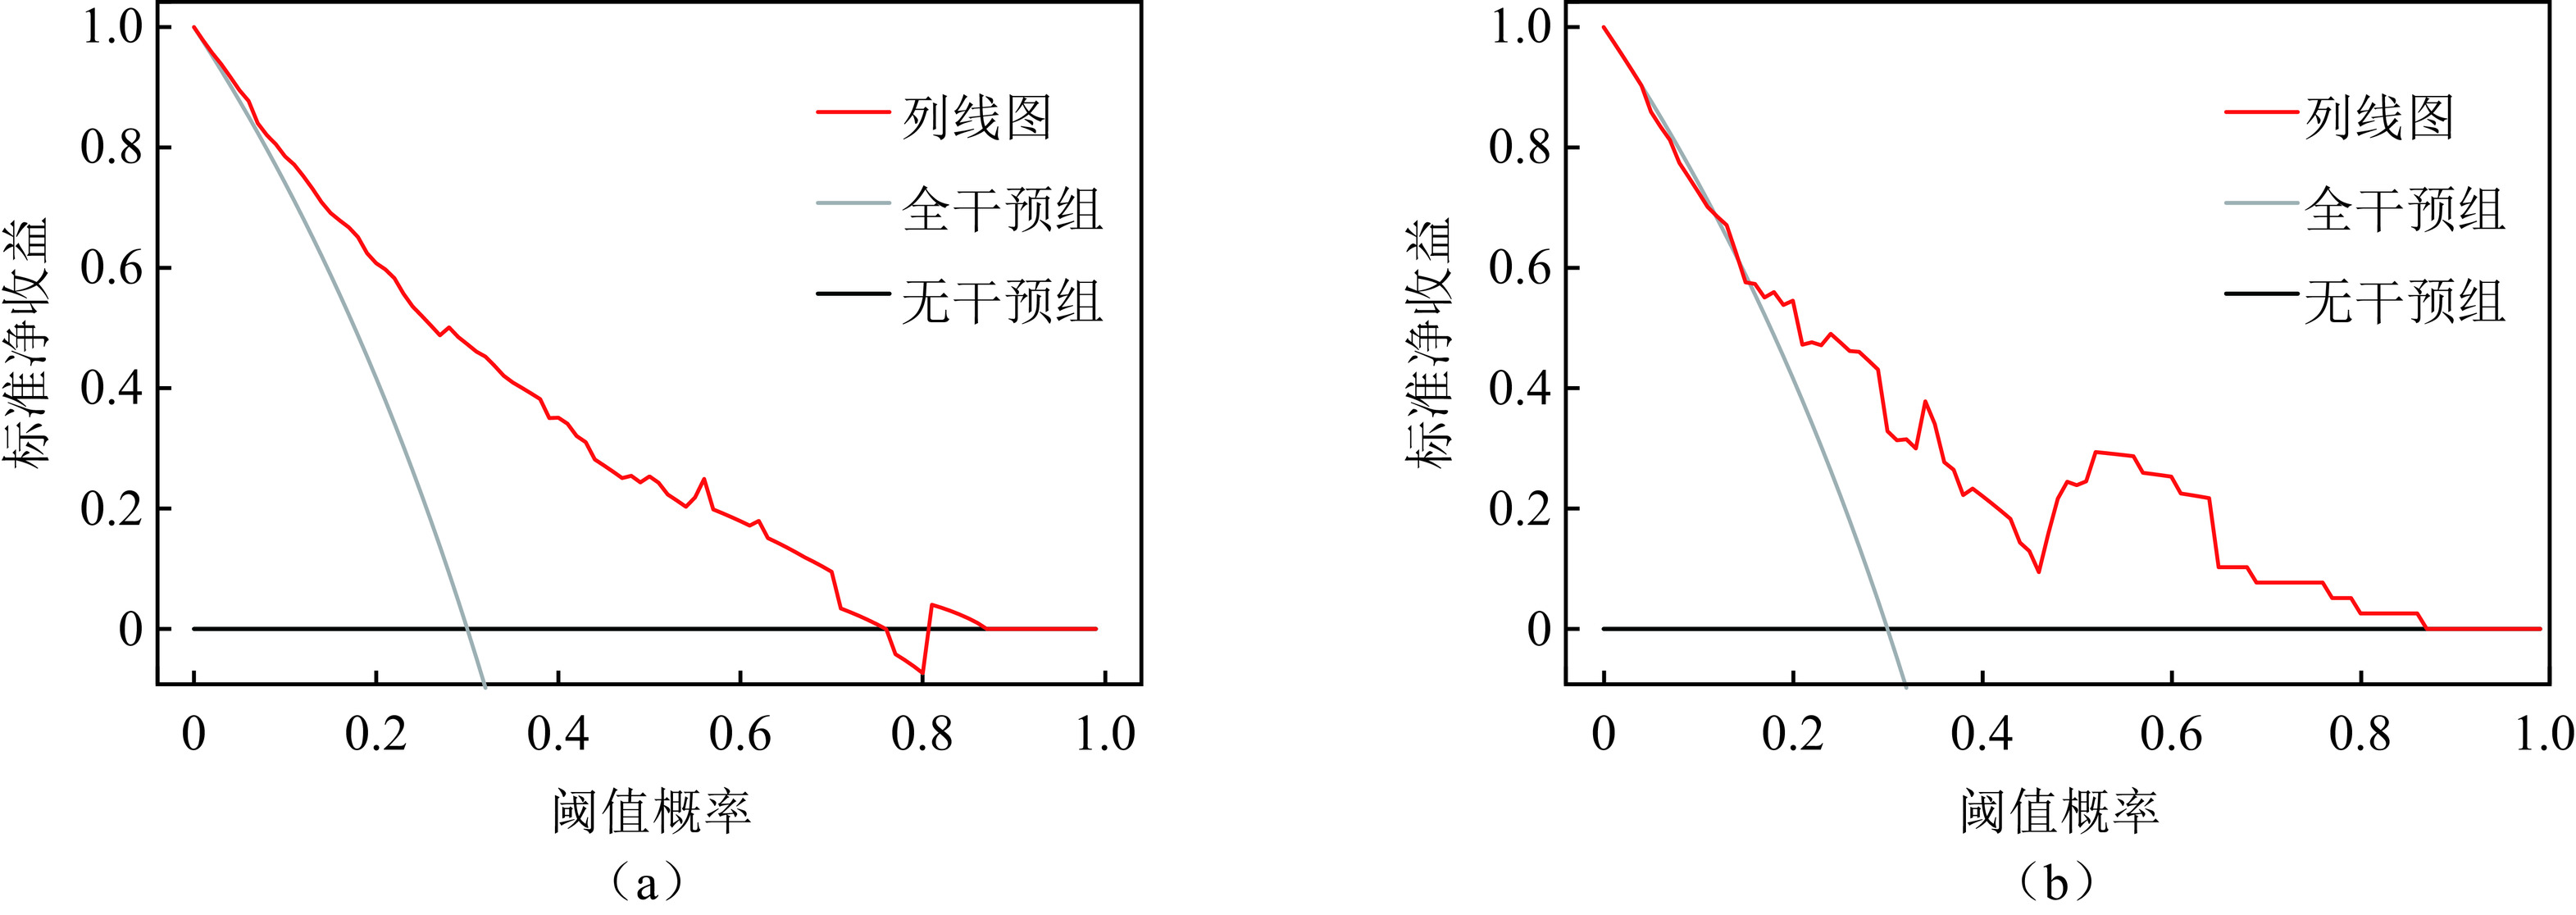

图 3 Nomogram预测CLNM的性能演示(界值为0.303)注:患者1,男性,44岁,PTC病例,CLNM阳性。CT平扫示右叶中下部类圆形病灶,内见钙化,与甲状腺被膜接触约75%(a),增强后不均匀强化(b),超声显示低回声区,境界清晰,边缘光整,约20.6×16.5×18.5 mm(c),对照Nomogram:男性(38分)+年龄 < 55岁(28分)+被膜接触 > 50%(100分)+最大径 > 10 mm(45分)=211分,对应的CLNM预测概率0.73。患者2,女性,37岁,PTC病例,CLNM阴性。右叶内不规则低密度结节,边缘与被膜无接触(d),增强后轻度强化(e),超声显示境界清晰,边缘不光整的低回声区,最大径约8.5 mm(f),对照Nomogram:年龄 < 55岁(28分)+边缘不规则(48分)=76分,对应的CLNM预测概率0.10。Figure 3. Performance of the nomogram for CLNM (cutoff=0.303)Nomogram的预测准确性和临床实用性用Calibration和DCA评价(图4和图5),Calibration显示预测概率和实际概率在训练组和验证组中一致性程度很高。DCA曲线表明,当个体患者预测概率在0.1到0.85范围内,Nomograms预测CLNM的净收益高于无预测组或全部干预组。